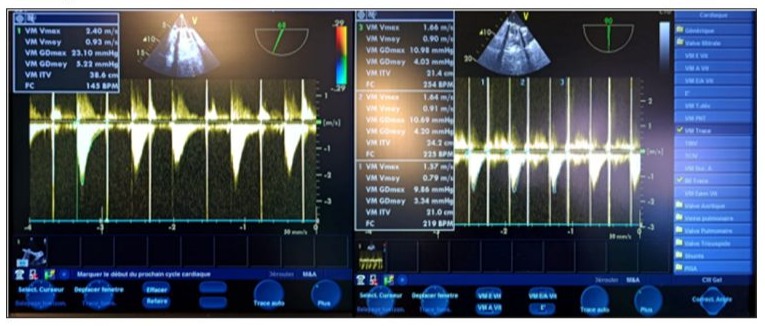

Figure 4: TEE 2D in the mid-esophageal view, transducer at 105 degrees (a; b), showing thrombi on the atrial side of both the internal and external leaflets of the mechanical valve on the aortic valve side as well as on the opposite side (black arrows), with a thickened appearance of the mechanical valve ring (red arrow) and multiple thrombi on the ventricular side (orange arrows).

Figure 5: TEE Doppler with the transducer at 105 degrees showing a very high mean transvalvular gradient of 27.85 mm Hg on continuous Doppler, with a calculated valve area of 109.4 cm² (a) in favor of stenosis, and severe thrombotic regurgitation with a mean gradient of 28.80 mm Hg (b) in favor of severe mitral regurgitation.